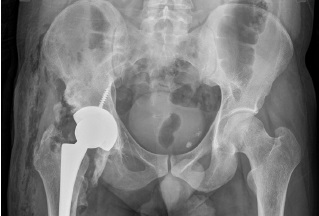

The anamnesis revealed that in 2008, the patient sustained multiple injuries during a traffic accident, namely, an open fracture of both bones of the left lower leg and an open craniocerebral injury. At the primary healthcare facility, cranial trepanation, primary surgical treatment of the left leg wound, plaster casting of the fracture were performed. The patient was in a coma for 1 month. After regaining consciousness, the patient demonstrated limited mobility in the right hip joint and a general decrease in sensitivity according to the hemitype in the right half of the body. Within 10 years, the pain syndrome and limited range of motion in the right hip joint progressed. Figure 1a presents a radiograph of the right hip joint, performed in 2018, in a state of ankylosis in presence of HO.

Fig. 1. X-rays of the right hip joint: a — before the first total hip arthroplasty; b — after surgery

In August 2018, the patient underwent total right hip arthroplasty (Zimmer Trilogy IT/CLS-Spotorno), with a sliding pairing of metal-crosslink polyethylene, head 36/−3 mm) (Fig. 1b).